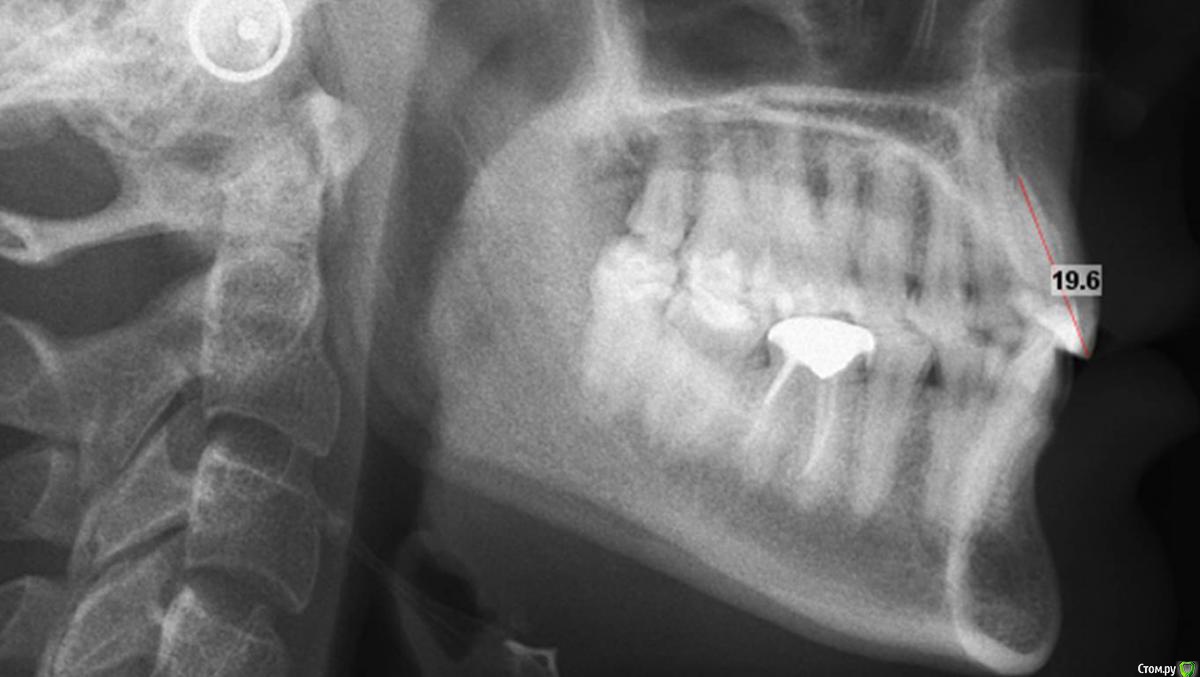

alekszander Опубликовано 10 декабря, 2015 Поделиться Опубликовано 10 декабря, 2015 Достойно.А можно рентген зубов,посмотреть соотношение корень коронка. Ссылка на комментарий

Сева северный Опубликовано 10 декабря, 2015 Автор Поделиться Опубликовано 10 декабря, 2015 Достойно.А можно рентген зубов,посмотреть соотношение корень коронка.Пациентка, реферативно, от ортодонта. Резцы короткие около 19 мм. Ссылка на комментарий

Сева северный Опубликовано 11 декабря, 2015 Автор Поделиться Опубликовано 11 декабря, 2015 (изменено) Как вы определяете когда надо делать хир.удлинение коронки, а когда просто удлинить без хирургии. По стертым режущим краям,похоже что не было нарушения прорезывания...зондировали до ЦЭС? Или по десневой улыбке скромной решили пойти апикально?Я сделал только планирование.... Ход мысли был следующий: Длина центральных резцов 19-20 мм. Длина коронковой части зуба центрального резца 7-8 мм. Оптимальная длина 10.5. По результату пациентка с мотивирована на ортодонтию , с коррекцией gammy smile. Решение по хирургии, примем по результатам ортодонтии. Изменено 11 декабря, 2015 пользователем Сева северный 1 Ссылка на комментарий